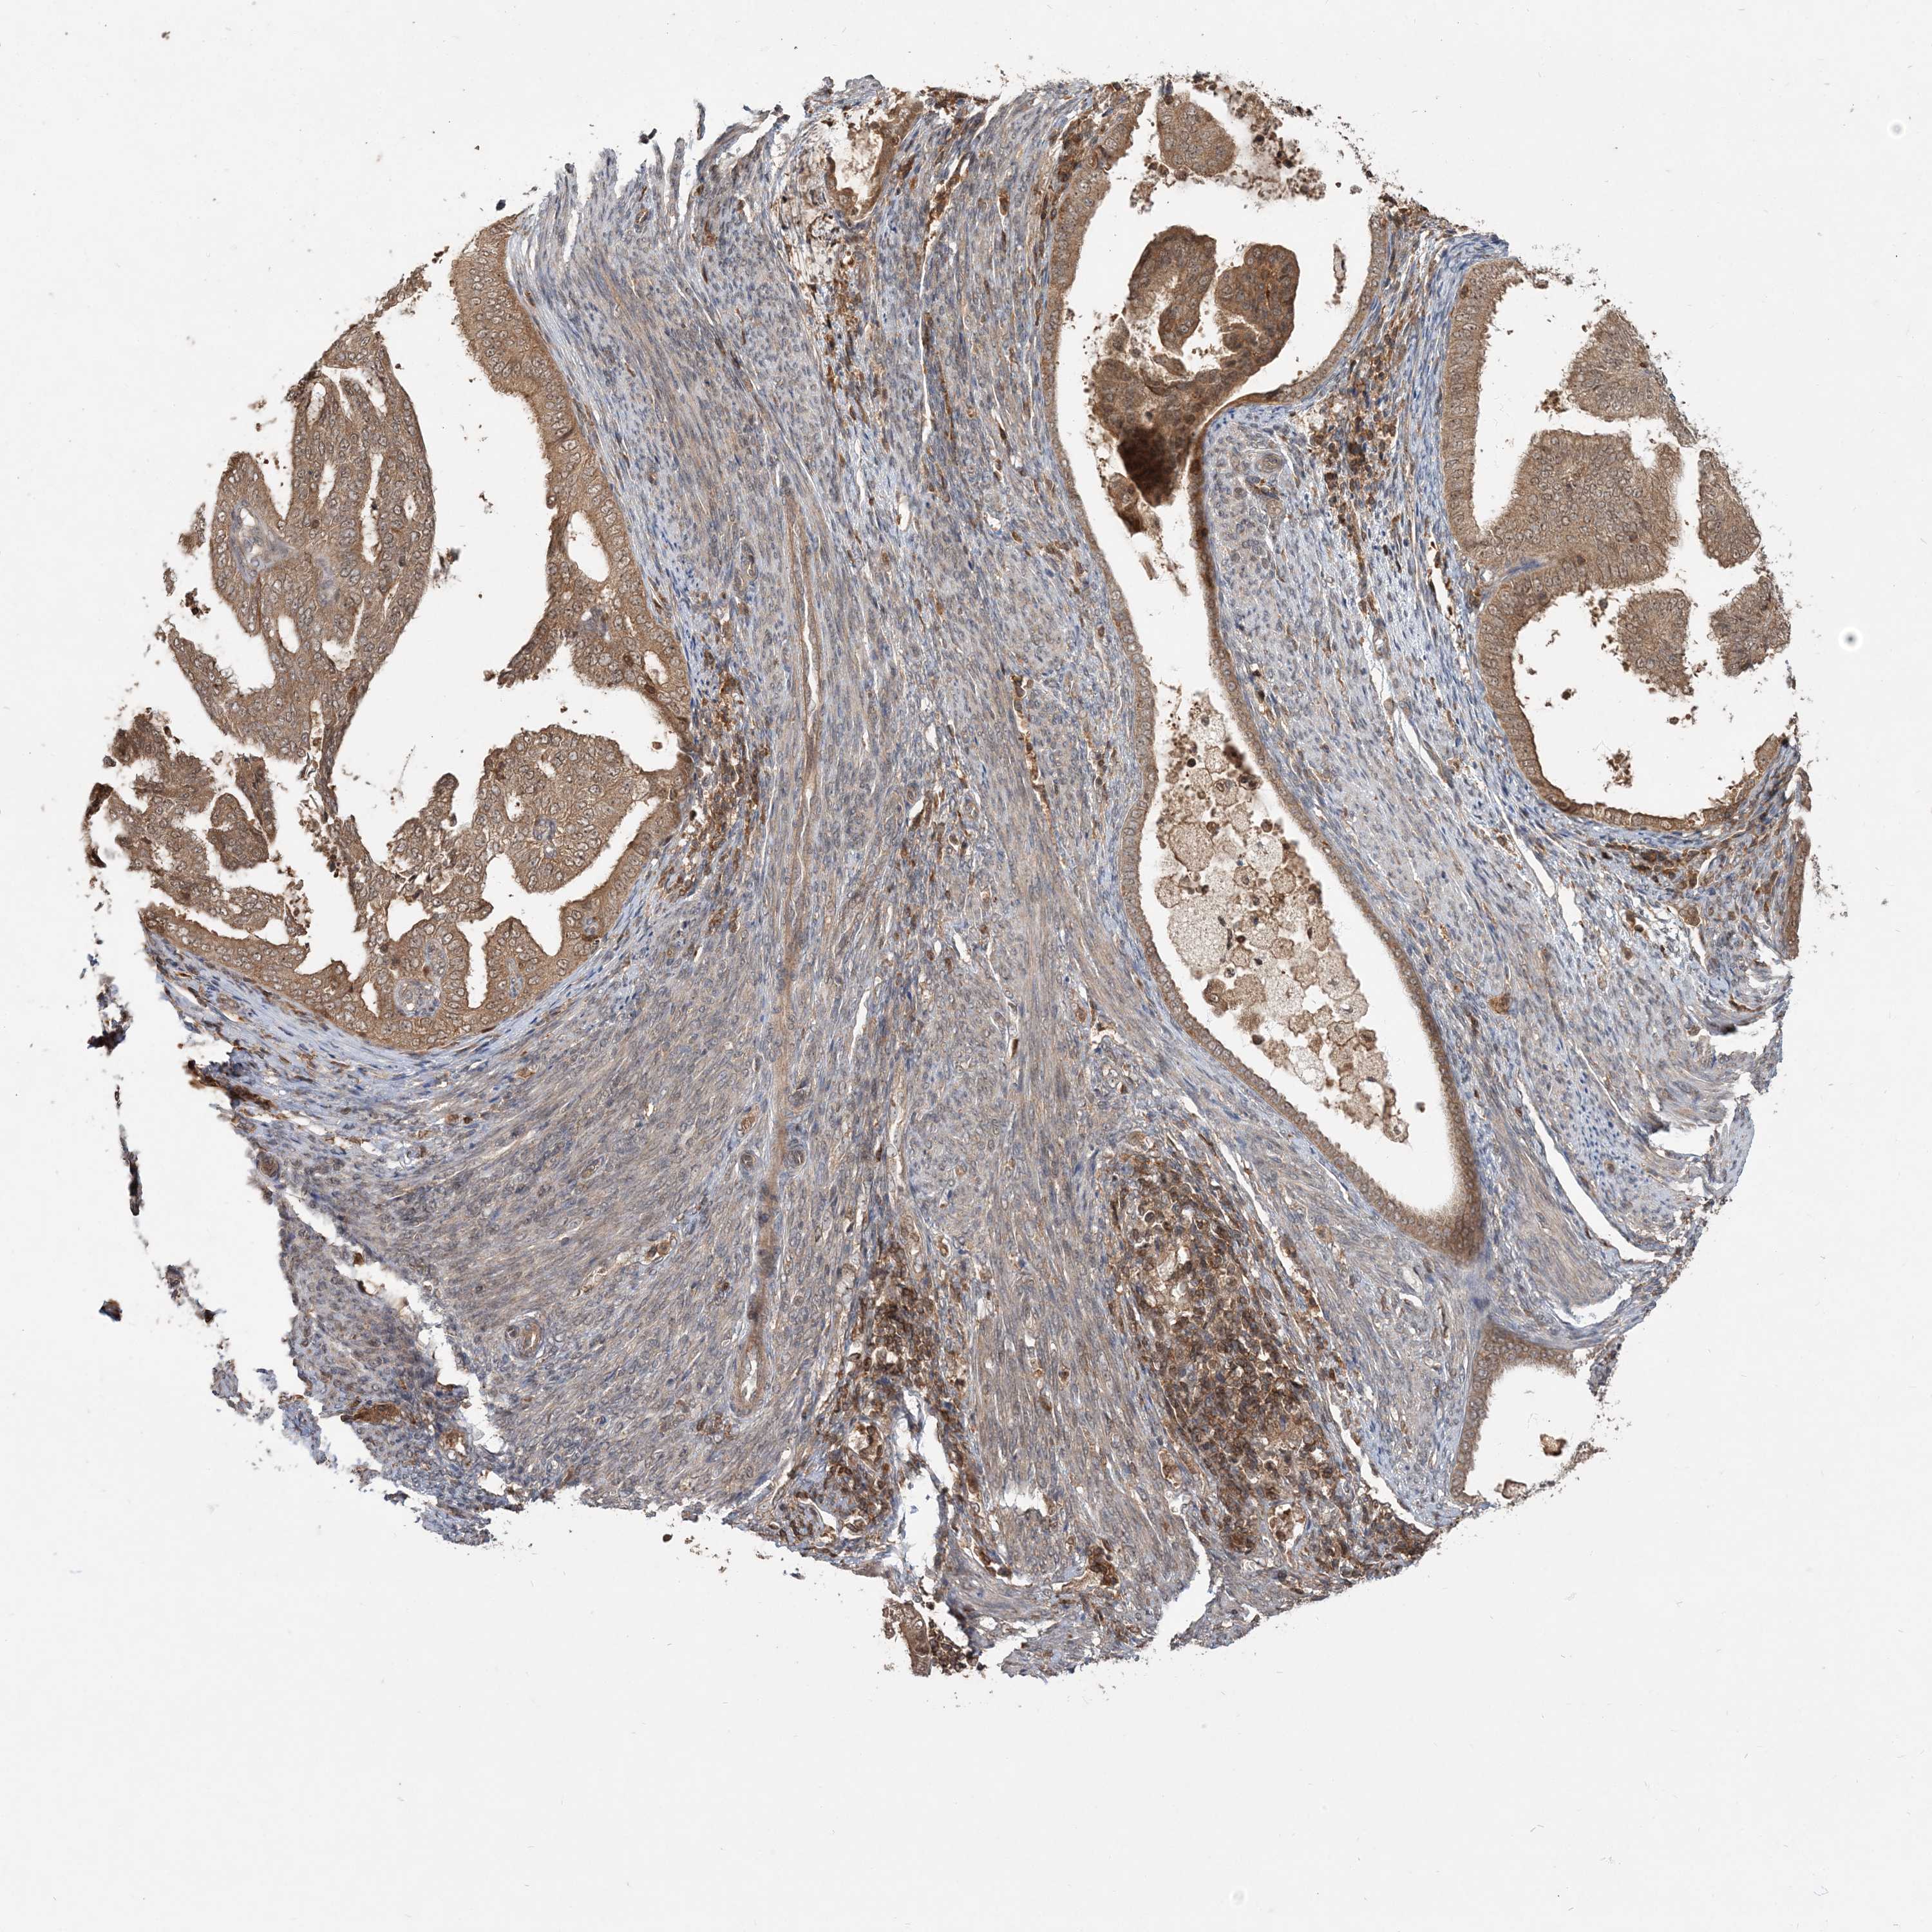

ENDOMETRIAL CANCER - Protein expressioni

A mouse-over function shows sample information and annotation data. Click on an image to view it in a full screen mode. Samples can be filtered based on level of antibody staining by selecting one or several of the following categories: high, medium, low and not detected. The assay and annotation is described here.

Note that samples used for immunohistochemistry by the Human Protein Atlas do not correspond to samples in the TCGA dataset.

Antibody stainingi

Antibody staining in the annotated cell types in the current human tissue is reported as not detected, low, medium, or high, based on conventional immunohistochemistry profiling in selected tissues. This score is based on the combination of the staining intensity and fraction of stained cells.

Each image is clickable and will lead to virtual microscopy that enables deeper exploration of all samples and also displays staining intensity scores, fraction scores and subcellular localization as well as patient and tissue information for each sample.

Antibody HPA076632

Antibody CAB037112

Staining

High

Medium

Low

Not detected

Intensity

Strong

Moderate

Weak

Negative

Quantity

>75%

75%-25%

<25%

None

Location

Nuclear

Cytoplasmic/membranous

Cytoplasmic/membranous,nuclear

Adenocarcinoma, NOS